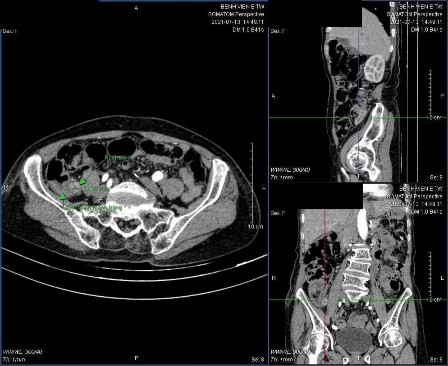

Hình 3.7: Biến chứng vỡ ruột thừa trên CLVT

3.2.3.4. Giá trị của CLVT trong chẩn đoán biến chứng vỡ RT Bảng 3.14: Giá trị của CLVT trong chẩn đoán biến chứng vỡ RT

Nhận xét: Có 5 trường hợp được chẩn đoán vỡ ruột thừa trên CLVT, tuy nhiên chỉ 4 trường hợp có vỡ thực sự. Có 7 bệnh nhân vỡ ruột thừa trên thực tế nhưng không phát hiện được trên CLVT.

Giá trị dự báo dương tính: PPV = 4/5

Giá trị dự báo âm tính: NPV = 105/112 = 93,8% Độ nhạy Se = 4/11

Độ đặc hiệu Sp = 105/106 = 99,1% Độ chính xác Acc = 93,2%